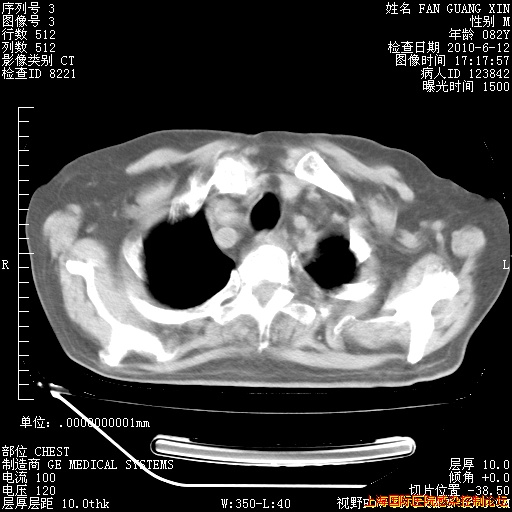

今天复查CT

今天CT

整整相隔30天的肺部CT好像有所好转啊。甲强龙减量第3天,需要观察体温。

海管,自昨日你和我通完话后,不知您岳父消化道症状有无缓解?体温怎样?阅读7.12日胸部ct,个人认为目前激素治疗是有效的,甲强龙减量是适宜的。因在抗痨治疗,需密切观察肝功、肾功能和血常规。不过,老年、长期住院和大量使用激素,很担心菌群失调发生